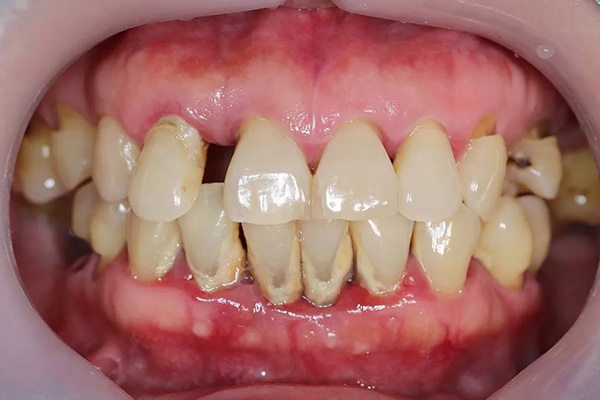

This procedure is normally undertaken to deal with gum recession, which is when the gum around the teeth wears away, exposing too much of the root. This can mean the roots are exposed to damage and decay, and be more sensitive than is comfortable.

For many, the concern is cosmetic, and many patients undergo a gum graft to improve the appearance of their smile.

The cause of gum recession varies, but it can come down to a number of factors, including gum disease, improper brushing, genetics, or aging.

Receding gums can make teeth look longer or uneven, but grafting helps restore a more natural gum line. It can be a real confidence booster, especially if you’ve been feeling self-conscious about your teeth.

When gums recede, the roots of your teeth can become exposed, and that often leads to increased sensitivity, especially to cold drinks or sweet foods.

A gum graft covers those exposed areas, which helps reduce sensitivity and makes eating and drinking more comfortable.